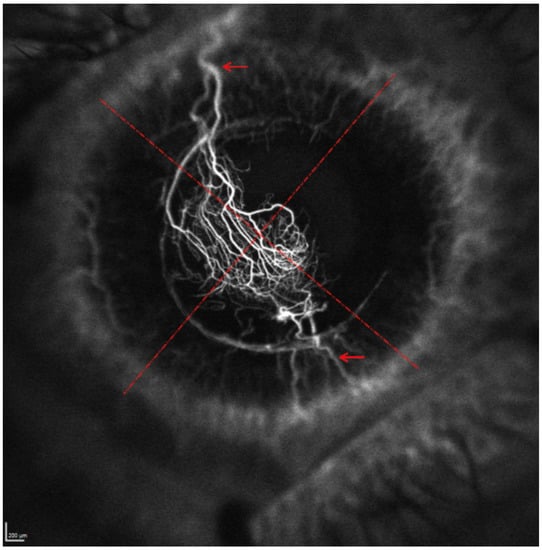

3.1. Lesion and CoNV Location

3.2. Order of Filling of CoNV